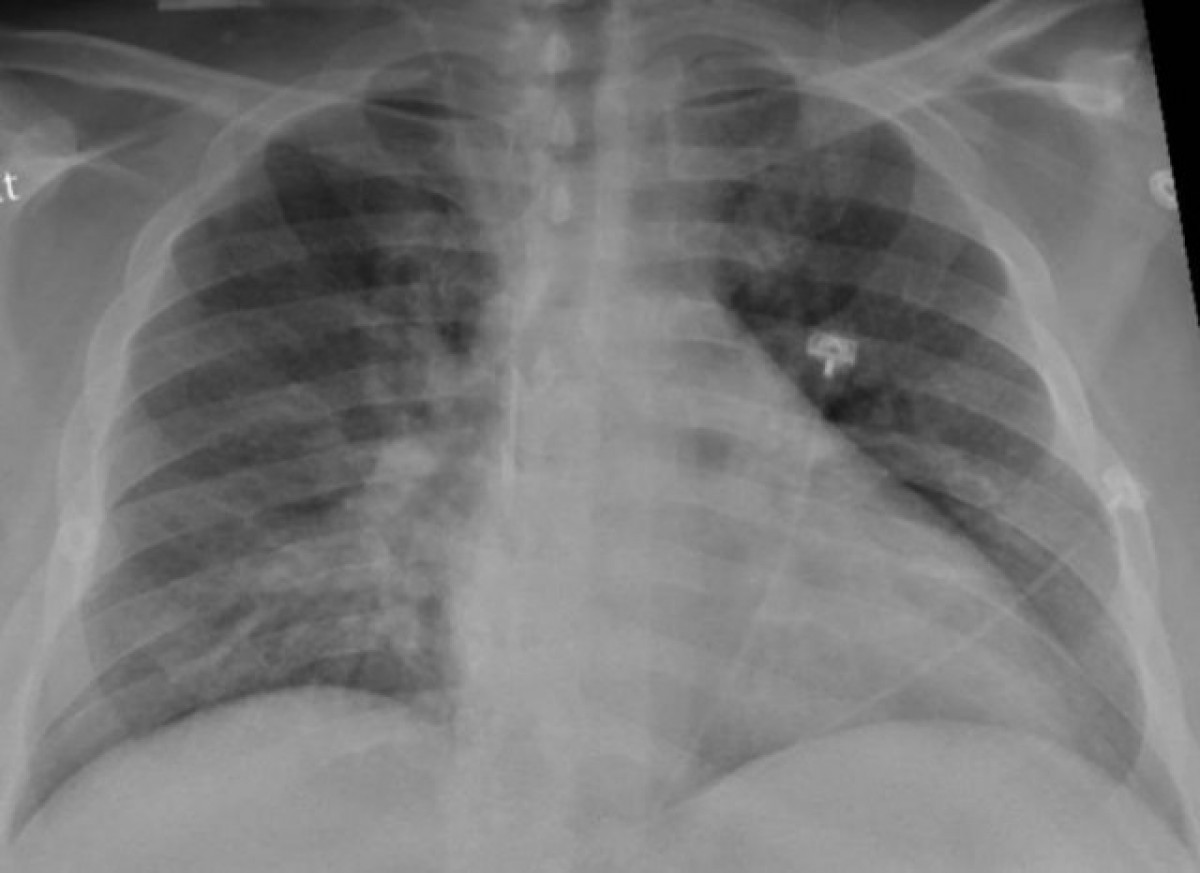

Radiografia de tòrax d'un pacient amb pneumònia